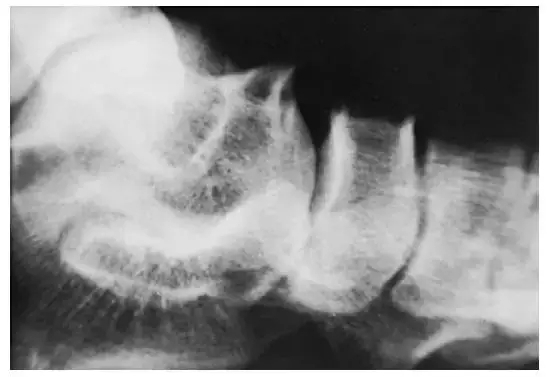

上述旋转由踝关节通过距下关节传导至跟骨和足部。关节炎,创伤,手术,或先天性异常等可导致距下关节运动功能丧失。而上述旋转功能丧失会导致该固定关节临近的关节如踝关节、跗横关节等应力增加,进而引发慢性疼痛。上述应力的增加可能会引起进一步损伤而导致球窝状踝关节(ball-and-socket ankle joint)的形成(图2)。此外在一个距下关节融合的患者还可能会出现距舟关节的损伤(图3)。

图3 距下关节融合后高应力导致的距骨骨折。